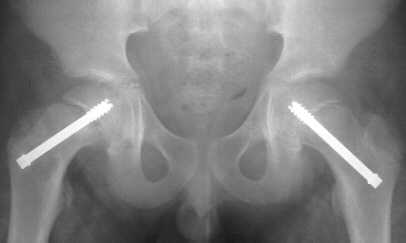

An AP pelvis and frog-leg lateral radiographs of both hips were obtained. On the AP pelvis radiograph, there was notable widening and irregularity of the proximal femoral epiphyseal growth plate, and Klein's line did not intersect the epiphysis. The frog-leg lateral view of the right hip demonstrated an obvious grade 1 slipped capital femoral epiphysis.

The patient was admitted to the hospital, placed on strict bedrest, and he had an in situ pinning of his right hip the next day. There were no postoperative complications, and he was discharged one day later. By the time of his follow-up visit three weeks later, he was riding his bike and had discarded his crutches. An AP pelvis and frog-leg lateral radiographs of both hips were obtained which were normal. At his three-month follow-up visit, the patient complained of a two week history of vague left hip pain. AP and frog-leg lateral radiographs revealed a grade 1 left slipped capital femoral epiphysis. He had an in situ pinning of his left hip the next day without complications .